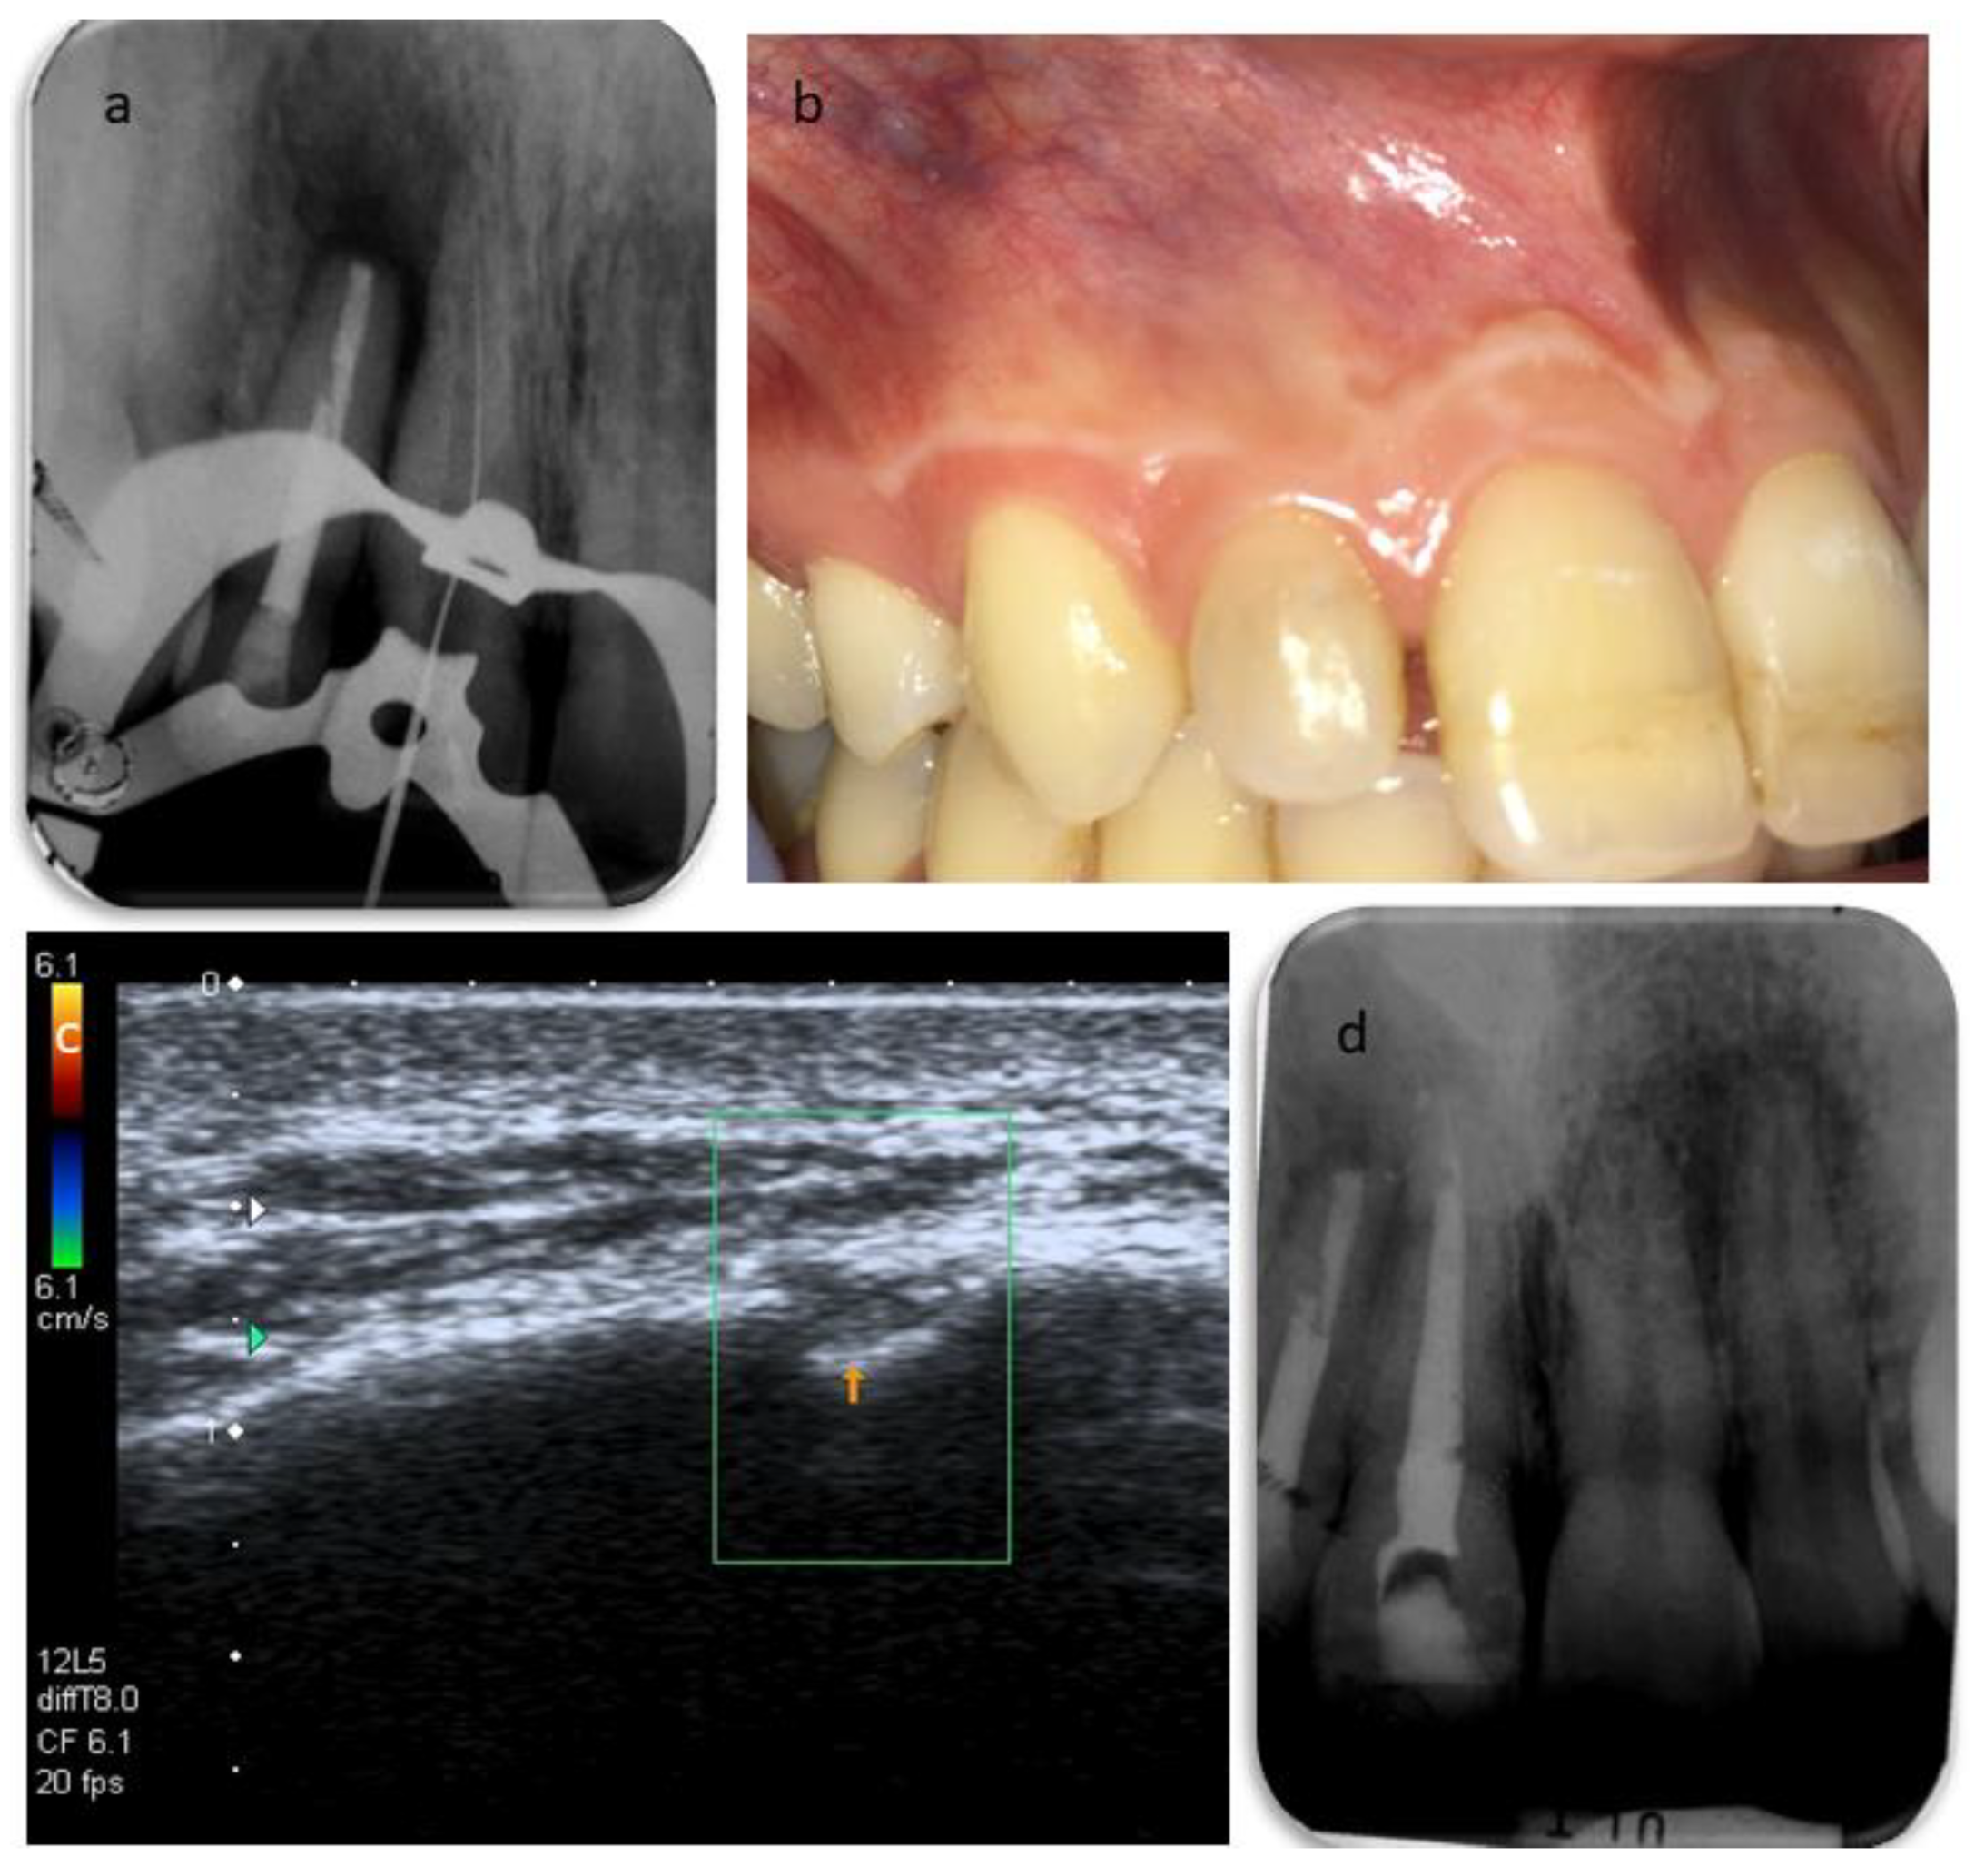

2. Case Report